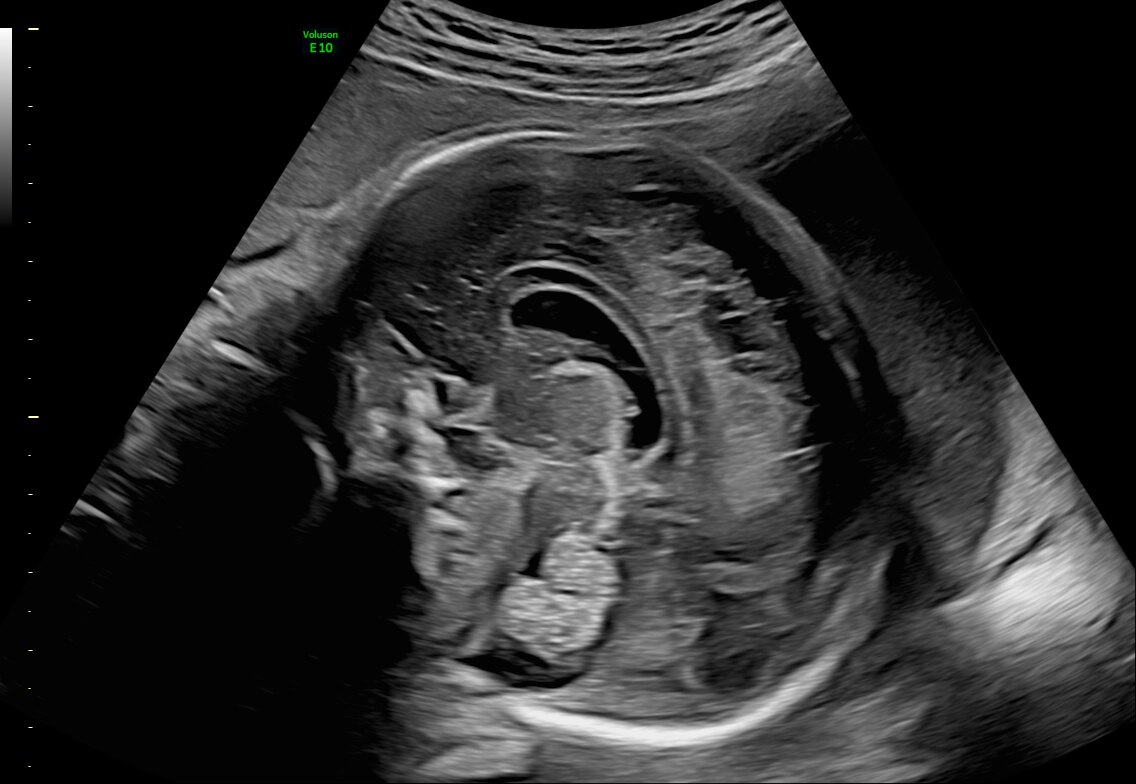

15-week fetal circulatory system with eSTIC and HD-Flow™